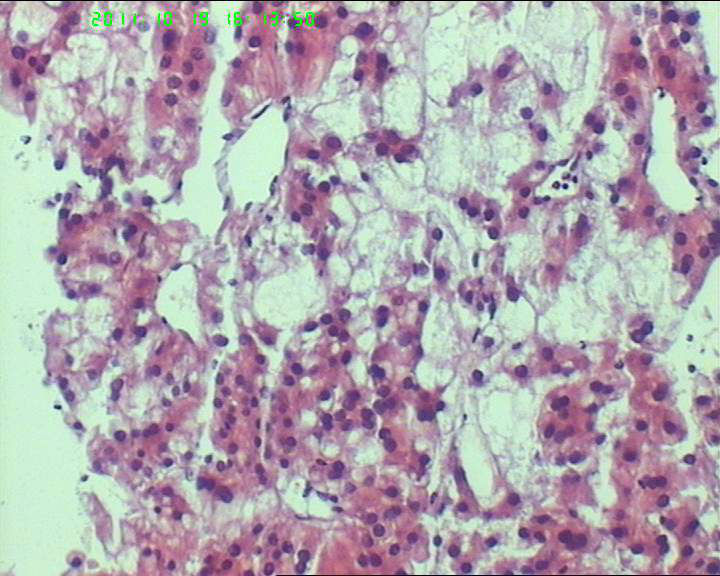

• 71岁男性肝脏占位,ct示低密灶,大三阳,afp高,转氨酶略高。该诊断什么呢?图1

图1